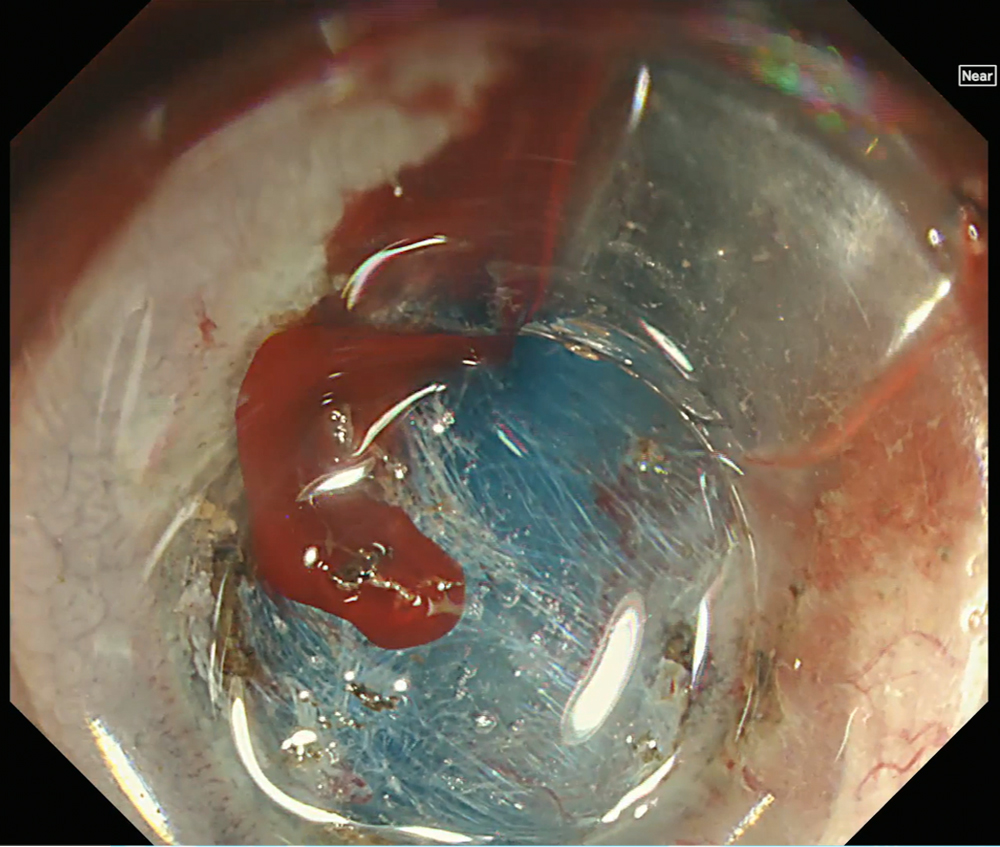

9. Bleeding in WLI

During ESD, active bleeding is observed on white light imaging.

10. Bleeding in RDI Mode 1

After activation of RDI mode 1, the bleeding point is more clearly visualized during ESD, facilitating prompt identification of the bleeding source compared with white light imaging.